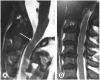

Methods: Upper cervical lesions in nine patients undergoing hemodialysis were surgically treated. Mean age at surgery was 61.6 years (range, 52-68 years), and the mean follow-up period was 45.4 months (range, 2-98 months). Patients had undergone hemodialysis for an average of 25.3 years (range, 16-40 years) at surgery. Seven patients with destructive spondyloarthropathy (DSA) of the upper cervical spine were treated with atlantoaxial or occipitocervical fixation. Two patients with retro-odontoid pseudotumors were treated with C1 posterior arch resection alone. Japanese Orthopedic Association (JOA) scores for cervical myelopathy, postoperative complications, postoperative radiography, and preoperative and postoperative occipital pain were evaluated.

Results: Mean preoperative and postoperative JOA score was 3.7 and 8.1, respectively. The seven patients with DSA had severe preoperative occipital pain that disappeared postoperatively. Postoperative radiography showed solid bone union in DSA cases and no instability in pseudotumor cases.